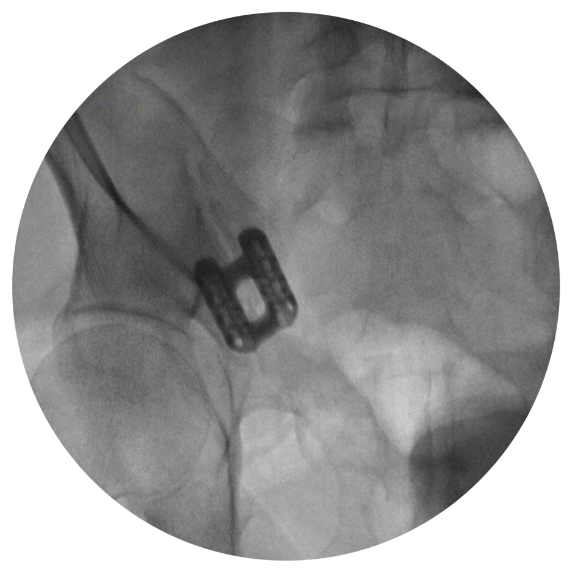

Minimally Invasive SI Joint Fusion

Using the Catamaran system from Tenon Medical, Dr. Burke permanently treats sacroiliac origin pain.

Catamaran SI Joint Fusion System

The implant is designed to stabilize and transfix the SI joint when placed in a strong cortical bone.